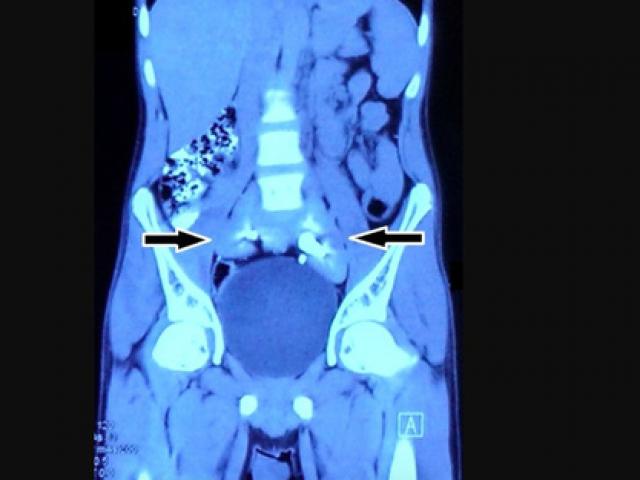

Bệnh nhân đang chạy thận nhân tạo tại BV Nông nghiệp.